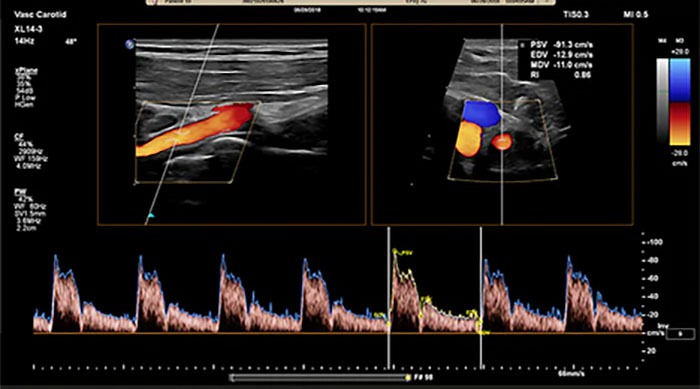

Doppler ultrasound, a special application of the technology, measures the direction and speed of blood cells as they move through vessels. Computers covert the sounds into graphs or pictures that represent the blood flow. The exam is used to evaluate blood flow through a blood vessel, including the body’s major arteries and veins in the abdomen, arms, legs, and neck.